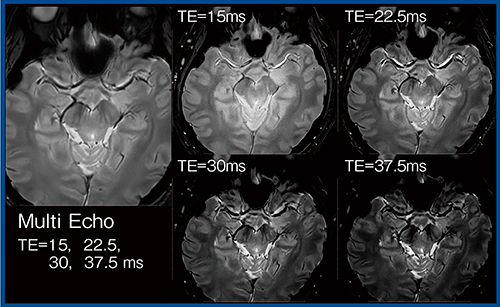

整形領域でよく用いられるT2*強調画像のマルチエコーは,複数エコーを収集し足し合わせる手法で,高いSNRとT2*強調コントラストが特長である。良好な白質/灰白質のコントラストが得られるほか,多発性硬化症の検出能がSEよりも良好と報告されている4)。そこで,マルチエコーT2*強調画像を用いてnigrosome-1を可視化できるか検討を行った(図5)。

nigrosome-1は,パーキンソン病ではドーパミン含有細胞の変性に伴い信号が不明瞭となる5)。3T MRIを用いても描出が難しいことが多いが,当院の正常例に対し,Vantage Centurianにてマルチエコーで撮像しAiCEを適用したところ,nigrosome-1がきわめて明瞭に描出された(図5 左)。

図5 マルチエコーT2*強調画像によるnigrosome-1の可視化(正常例)